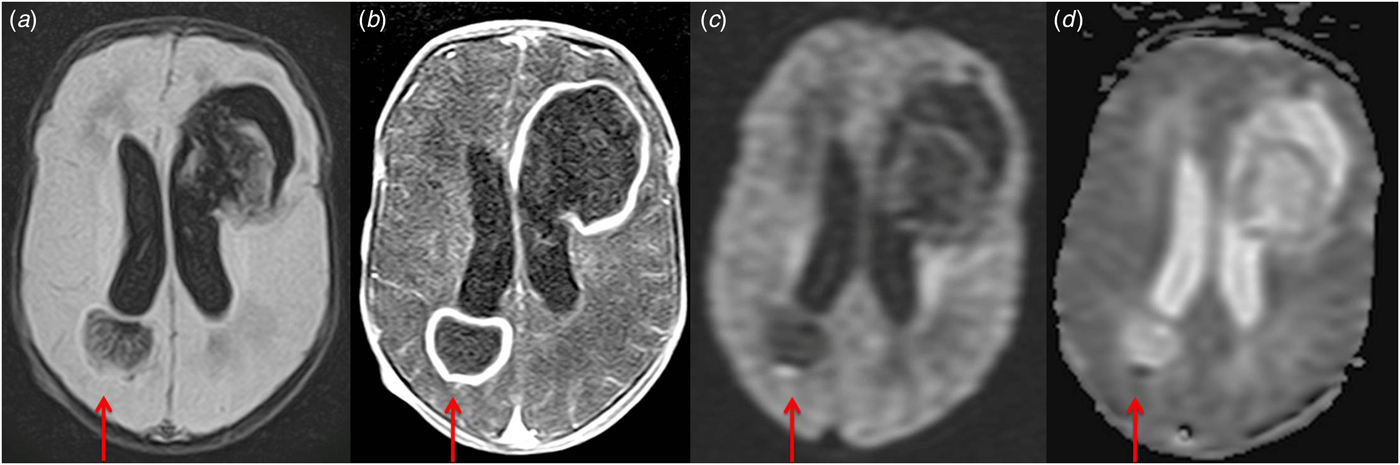

Fig. 1. Presence of two focal lesions in frontal and temporoparietal lobes with a hyperintense on fluid attenuation inversion recovery (FLAIR) images (a) with a hypointense rim with ring enhancement (b). The central core of the masses restricts strongly on the diffusion-weighted imaging (DWI) (c) and apparent diffusion coefficient map (ADC) (d). MRI features are consistent with cerebral abscesses.